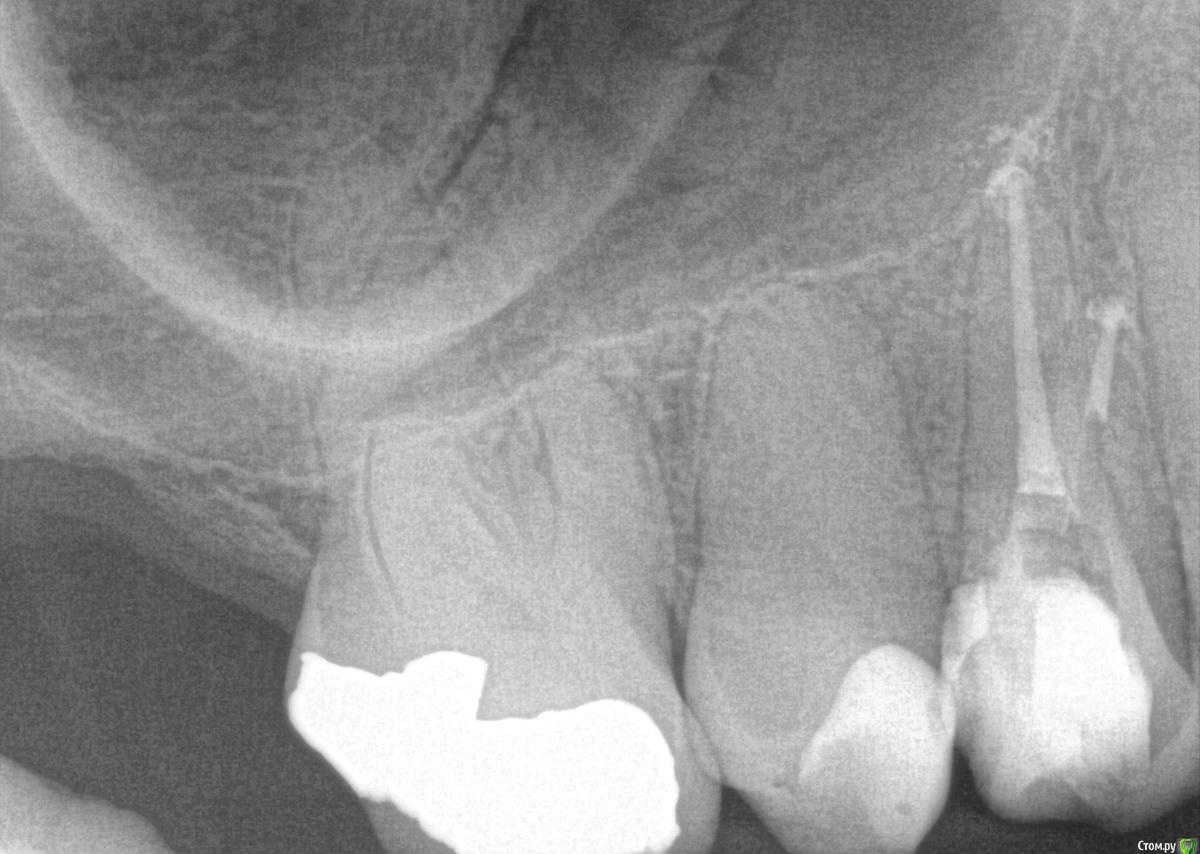

Rim3 Опубликовано 1 декабря, 2015 Поделиться Опубликовано 1 декабря, 2015 Уважаемые стоматологи, помогити пожалуйста! Во время пломбировки каналов верхнего бокового зуба с правой стороны у меня возникла резкая боль в районе синуса. Боль ушла через 3 -5 минут и врач настоял на продолжении лечения. Далее у меня опухла вся щека и появились синяки под глазами и щекой. Мне назначили стероиды и антибиотики. Как я позже поняла это было выведение гипохлорита натрия за пределы корня и травма. Теперь опухоль спала и синяки прошли. Я еще очущаю дискомфорт и некую болезненность в этой области.У меня теперь возник вопрос по поводу качества проведенного лечения каналов. Я собиралась закрыть зуб коронкой, но теперь сомневаюсь. Как вы считаете глядя на снимки, качественно ли запломбированы каналы? Что если не только гипохлотит натрия, но и гутаперча вышла за пределы корня. Возможны ли осложнения в будущем и операция по удалению лишнего материала? Ссылка на комментарий

anvladd Опубликовано 1 декабря, 2015 Поделиться Опубликовано 1 декабря, 2015 (изменено) Сделано хорошо,боли пройдут. Изменено 1 декабря, 2015 пользователем anvladd 3 Ссылка на комментарий